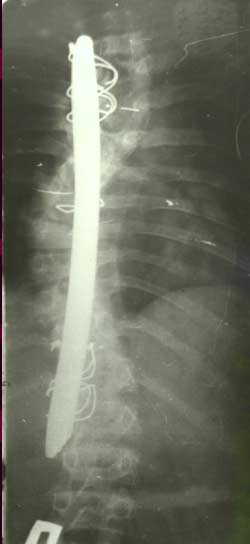

Л.Л.

Роднянский предложил для коррекции

сколиотической деформации одно-пластинчатый

эндокорректор. Методику характеризовала

малая травматичность и безопасность

оперативного вмешательства. Однако,

недостаточная жесткость конструкции,

малое число блоков крепления корректора

не позволяли оперировать тяжелые формы

деформации. В случаях вмешательства у

пациентов с начальной стадией заболевания,

с деформацией I-II степени не удавалось

избежать прогрессирования искривления.

В послеоперационном периоде происходила

достаточно быстрая потеря коррекции и

в общем она составляла приблизительно

40%. Кроме этого достоверно нарастала

ротационная деформация позвоночника

на вершине искривления.

Начиная с

80-х годов, благодаря тесному многолетнему

сотрудничеству инженеров отдела

медицинской техники ГП КРАСМАШ завода,

научно-производственного центра МЕДИЛАР,

Института Восстановительной медицины

и кафедры травматологии и ортопедии

Красноярской Государственной медицинской

Академии была внедрена новая конструкция,

которая принципиально отличается от

всех предыдущих, но, в тоже время,

сохранила их главное рациональное

зерно.

Само оперативное вмешательство требует

строжайшего соблюдения технологической

дисциплины, использование специального

инструментария и, естественно, специально

изготовленных пластин и деталей

крепления. Импровизации при операциях

на позвоночнике недопустимы. Все

оперативное вмешательство занимает от

2 до 3 часов.

Нами проведен анализ 209 случаев

оперативного лечения сколиотической

деформации II - IV степени с использованием

двухпластинчатого эндокорректора с

многоуровневой фиксацией. Срок наблюдения

составил от 1 до 4-5 лет с наличием

корректора и от 1 до 3 лет после его

удаления. Средний возраст 13,8 года.

Врожденный сколиоз был только в 3,83%

случаев. Деформация с наименьшим углом

по Коббу составила 21°, с наибольшим

124°. Основное число прооперированных

больных было с углом искривления в

диапазоне 31°-70°. Среди них у 43% угол

искривления составил 51°- 60°.